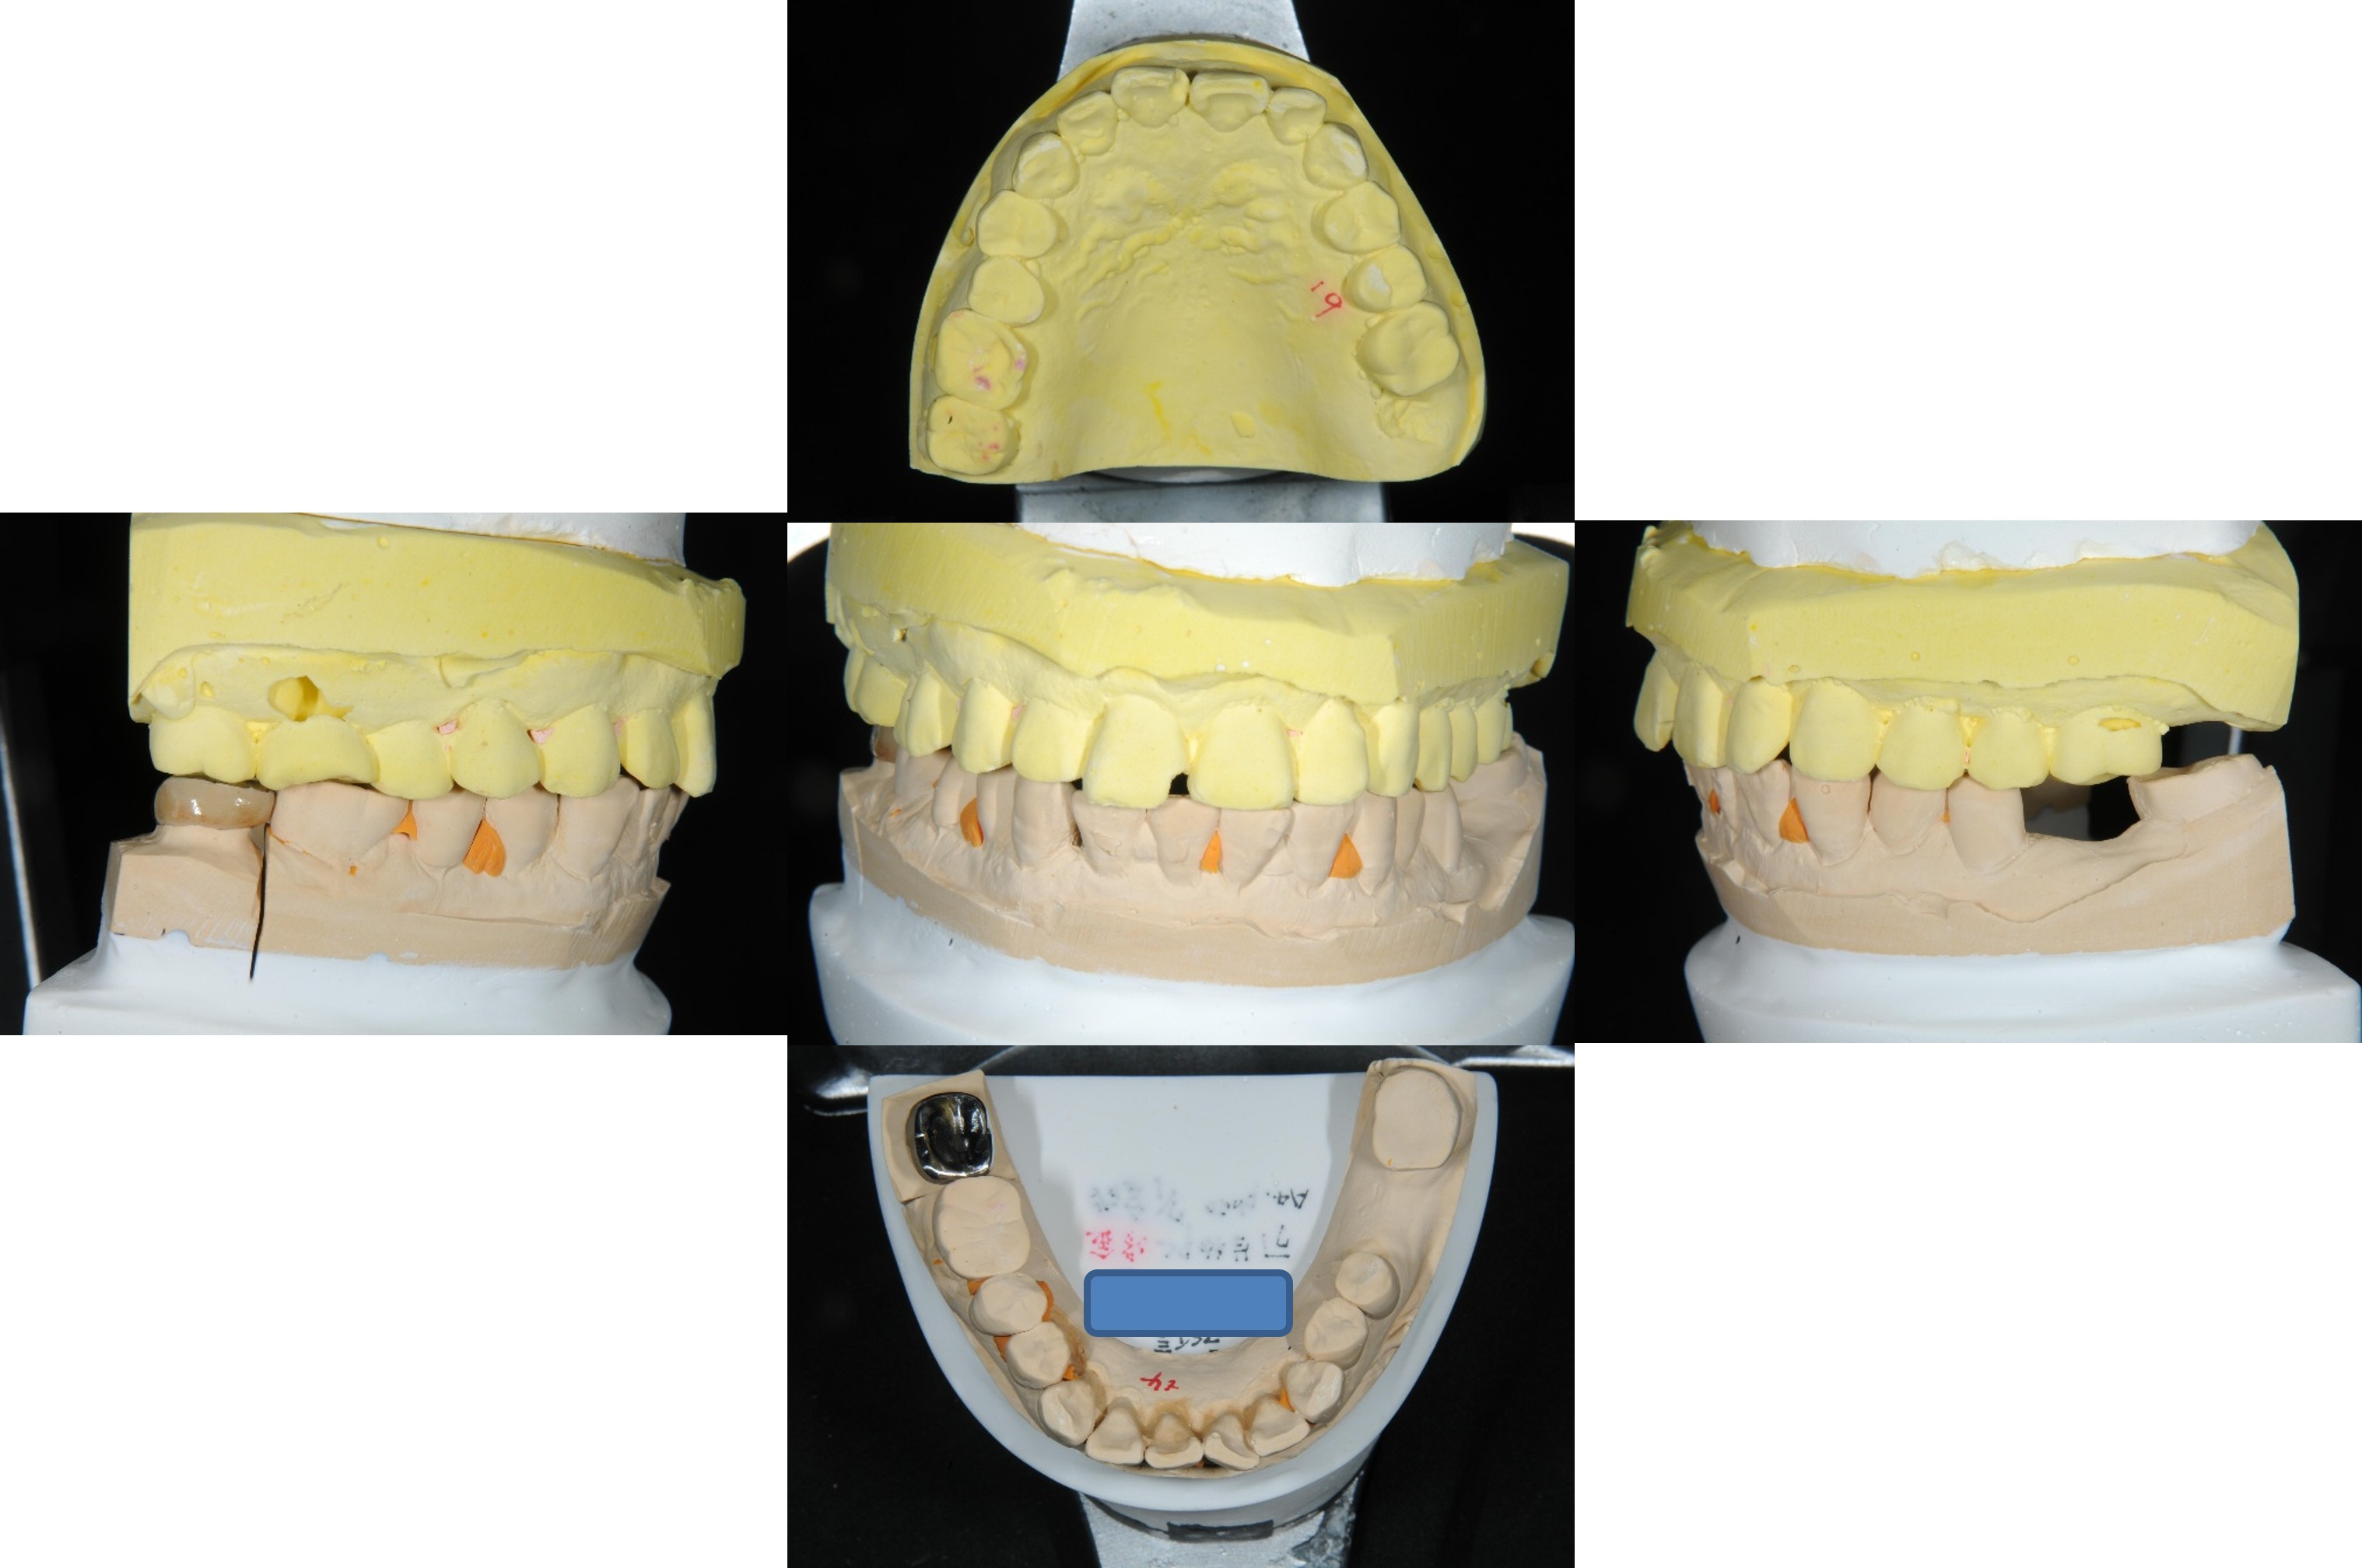

取面弓,上咬合器

製作固定假牙

因受力考量,製作金屬燒付瓷牙